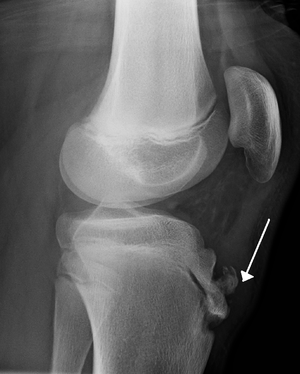

Lateral view X-ray of the knee demonstrating fragmentation of the tibial tubercle with overlying soft tissue swelling. | |